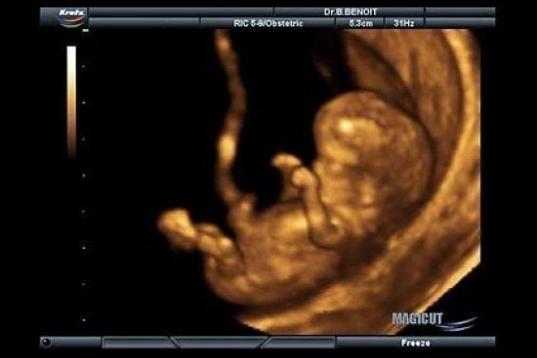

En esta galería puedes ver en fotos como es el desarrollo de un feto de semana en semana:

Desarrollo del feto, en fotos